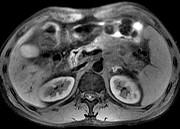

问题 男45岁、腹部胀痛不适、胃纳减退、体重减轻、中腹部可触肿块,影像检查如图,应诊断为 ( )

选项 A.急性胰腺炎 B.慢性胰腺炎 C.胰腺体尾部癌 D.胰岛细胞瘤 E.腹膜后淋巴结结核

答案 C